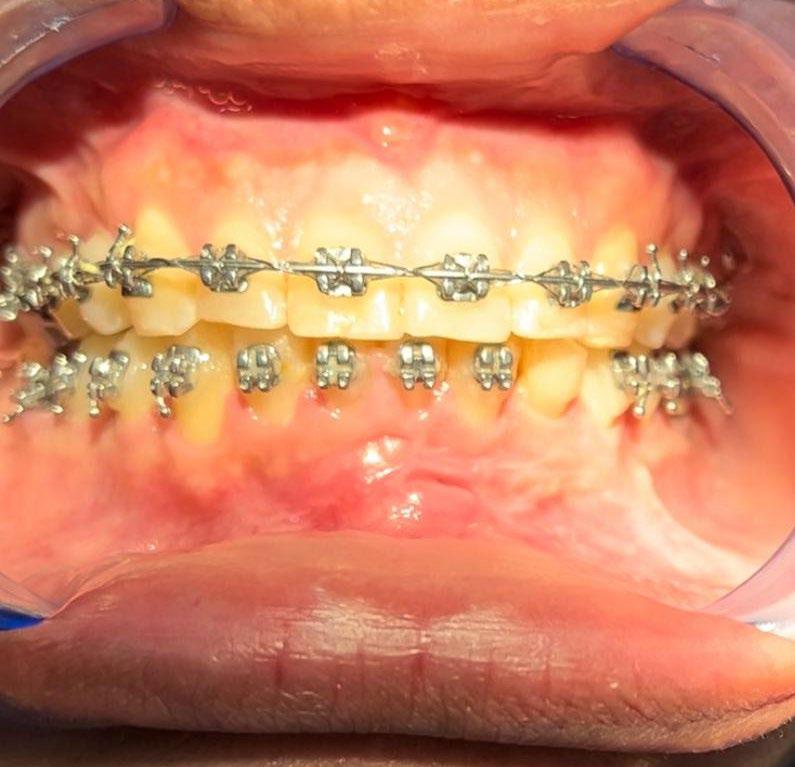

El tratamiento se realizó en las siguientes fases: la fase prequirúrgica incluyó la alineación, nivelación y la

extracción de los segundos premolares superiores e inferiores, con cierre de espacios. En la fase quirúrgica, se realizó una mentoplastia de avance e implantes en la zona malar. La fase postquirúrgica consistió en el detallado-retención. La aparatología utilizada fueron brackets de prescripción Roth .022 × .028; se colocaron bandas en los primeros molares superiores e inferiores, con tubos punteables en los O.D. 16, 26, 36 y 46, y tubos bondeables en el O.D. 27, además de un arco transpalatino y un arco lingual.

El tratamiento se realizó en las siguientes fases: la fase prequirúrgica incluyó la alineación, nivelación y la extracción de los segundos premolares superiores e inferiores, con cierre de espacios.

Figura 4. Lateral derecha.

Figura 5. Intraoral de frente e izquierda.